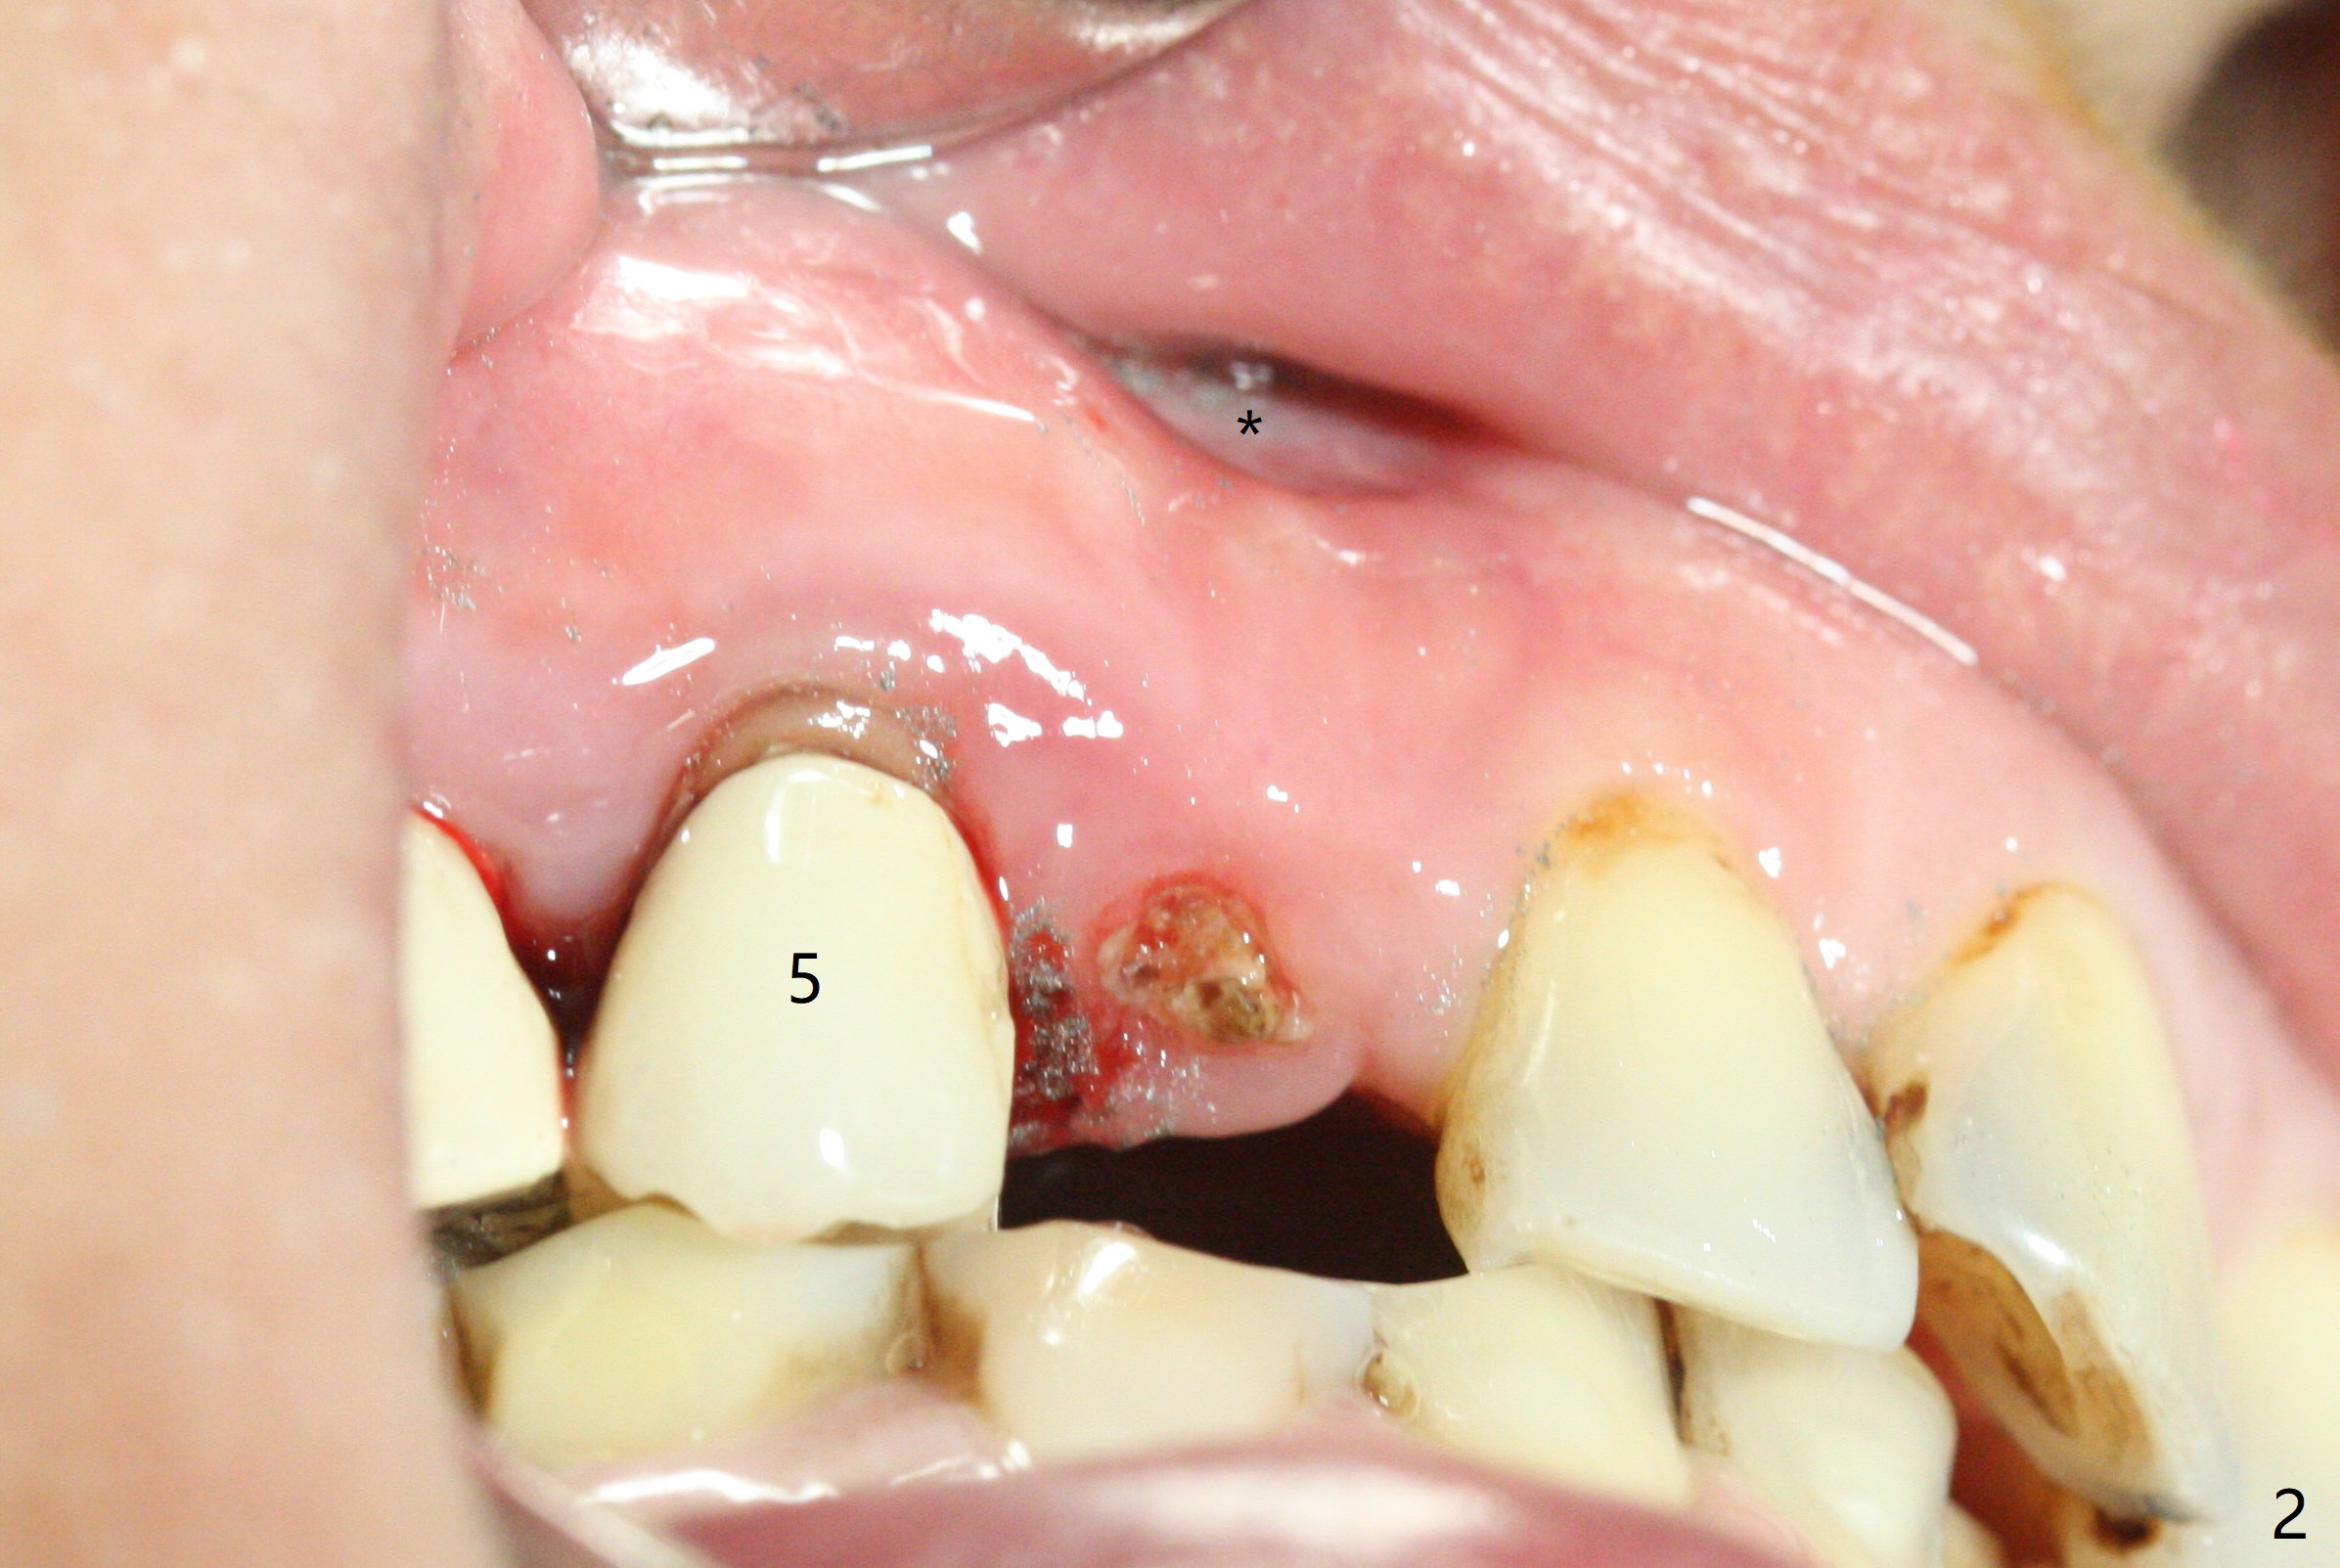

After removal the pontic of a cantilever FPD (Fig.1), a residual root is found at #6 with the buccal concavity (Fig.2 *). The ridge is narrow with flap elevation (Fig.3). PA taken with a 1.2 mm drill for 14 mm shows a horizontally impacted canine (Fig.4: #6). When the osteotomy is finished without apparently buccal perforation (Fig.5), the trajectory is buccal. When a 3x14 mm (12.5 mm in bone) 15 degree angled 1-piece implant is placed with normal trajectory (Fig.6), the buccal plate is perforated. As the implant is redirected so that the apical end of the implant does not stick out buccally, the trajectory returns buccal (Fig.7). The buccal aspect of the abutment is heavily reduced for an immediate provisional. The perforation is repaired with Vanilla Graft and Collagen Dressing before suturing. CT should have been taken preoperatively; the osteotomy should have been initiated as palatal as possible, as compared to that in Fig.5. When the 1st drill is used. it should be checked for restoration. An angled abutment does not help the trajectory substantially. The implant is loose 1.5 months (partially due to mastication); after retightening, CT is taken (Fig.8). The implant is within the bone. If the implant becomes loose again, extract the impacted canine and place the longest implant (22 mm) palatally. The implant is stable nearly 4.5 months postop (Fig.9). The patient is not satisfied with buccally-placed crown. The implant is removed with bone graft 6 months postop.